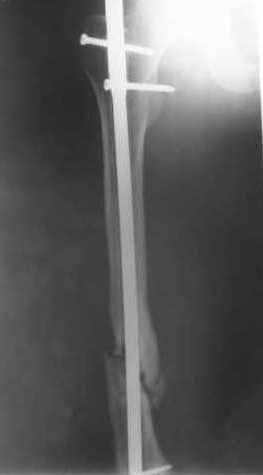

27 марта выполнено удаление блокирующих винтов (сломанный винт пришлось высверливать цапфен-бором), сломанного штифта (дистальный фрагмент удален через канал, образованный разверткой из коленного сустава - image 4),

рассверливание костно-мозгового канала, реостеосинтез штифтом UFN (при проведении штифта в дистальном отломке мы использовали поляризующий винт, диаметр штифта 10 мм). После операции в связи гемартрозом дважды (на 1 и 3 сутки) выполняли пункцию коленного сустава. Сейчас признаков скопления жидкости в полости сустава нет. Послеоперационные рентгенограммы - images 5, 6, 7.